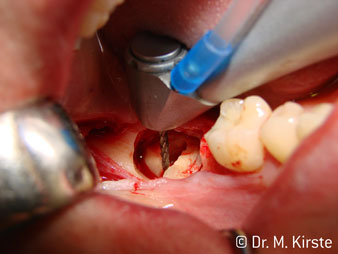

Угол 45° наконечника был выбран специально с учетом широкого круга преимуществ. Коллеги, которые работают в хирургии, и для которых этот наконечник был изначально создан, быстро оценят возможность эффективно работать в очень стесненном пространстве. В частности, при удалении зуба мудрости (рис. 2) не нужно сильно раздвигать мягкие ткани в области щеки (рис. 3). Конструкция головки наконечника в сочетании с небольшим поворотом головки во время препарирования позволяет быстро и безопасно выполнять работу в области задних коренных зубов.

Угловой наконечник с углом 45° очень удобно держать в руках. Вы почти сразу отметите, что рабочая головка имитирует угол наклона вашего указательного пальца, поэтому нужное движение легко переносится на пару воображаемых сантиметров параллельно кончику (рис. 1)".

Fig. 1